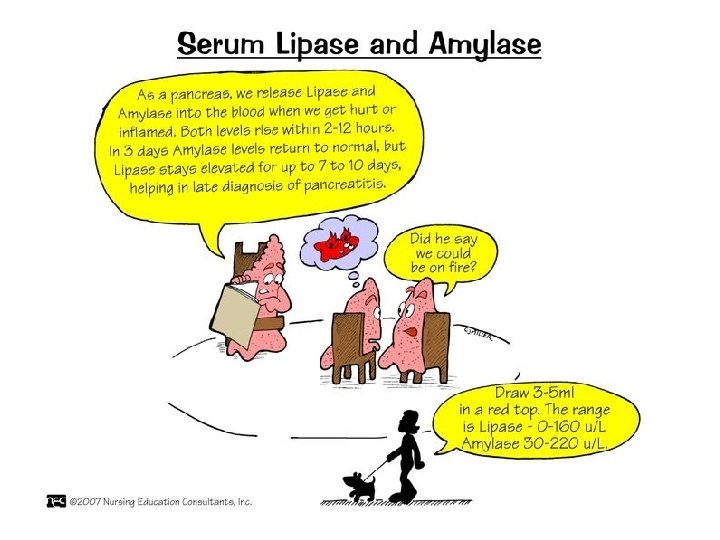

• DIAGNOZA DIFERENCIALE: - Appendisiti (ne fazen fillestare) - Pankreatiti - Patologjite renale dexter: infeksion apo kalkul ne ureter: *Anamneza *Ekzaminime laboratorik (urine) *Ekzaminime radiologjike te aparatit urinar

• DIAGNOZA DIFERENCIALE: - Me peritonitin akut nga ruptura te ndryshme si e apendiksit - Barra ekstrauterine - Pankreatit hemoragjik - Torsion ovarial

EKZAMINIMET LABORATORIKE: - Hemogram: Leukocitoze - Ekzaminimi i urines: per diagnoze diferenciale DIAGNOZA DIFERENCIALE: - Kolecistit - Kolika renale dexter - Ulcer gastroduodenale e perforuar - Okluzion intestinal